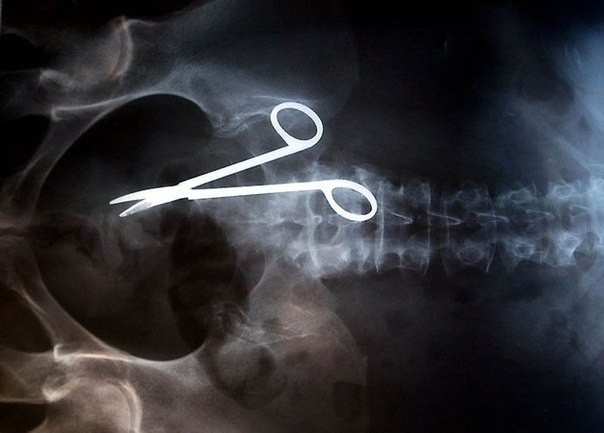

4) Tijeras quirúrgicas olvidadas dentro del cuerpo de un paciente